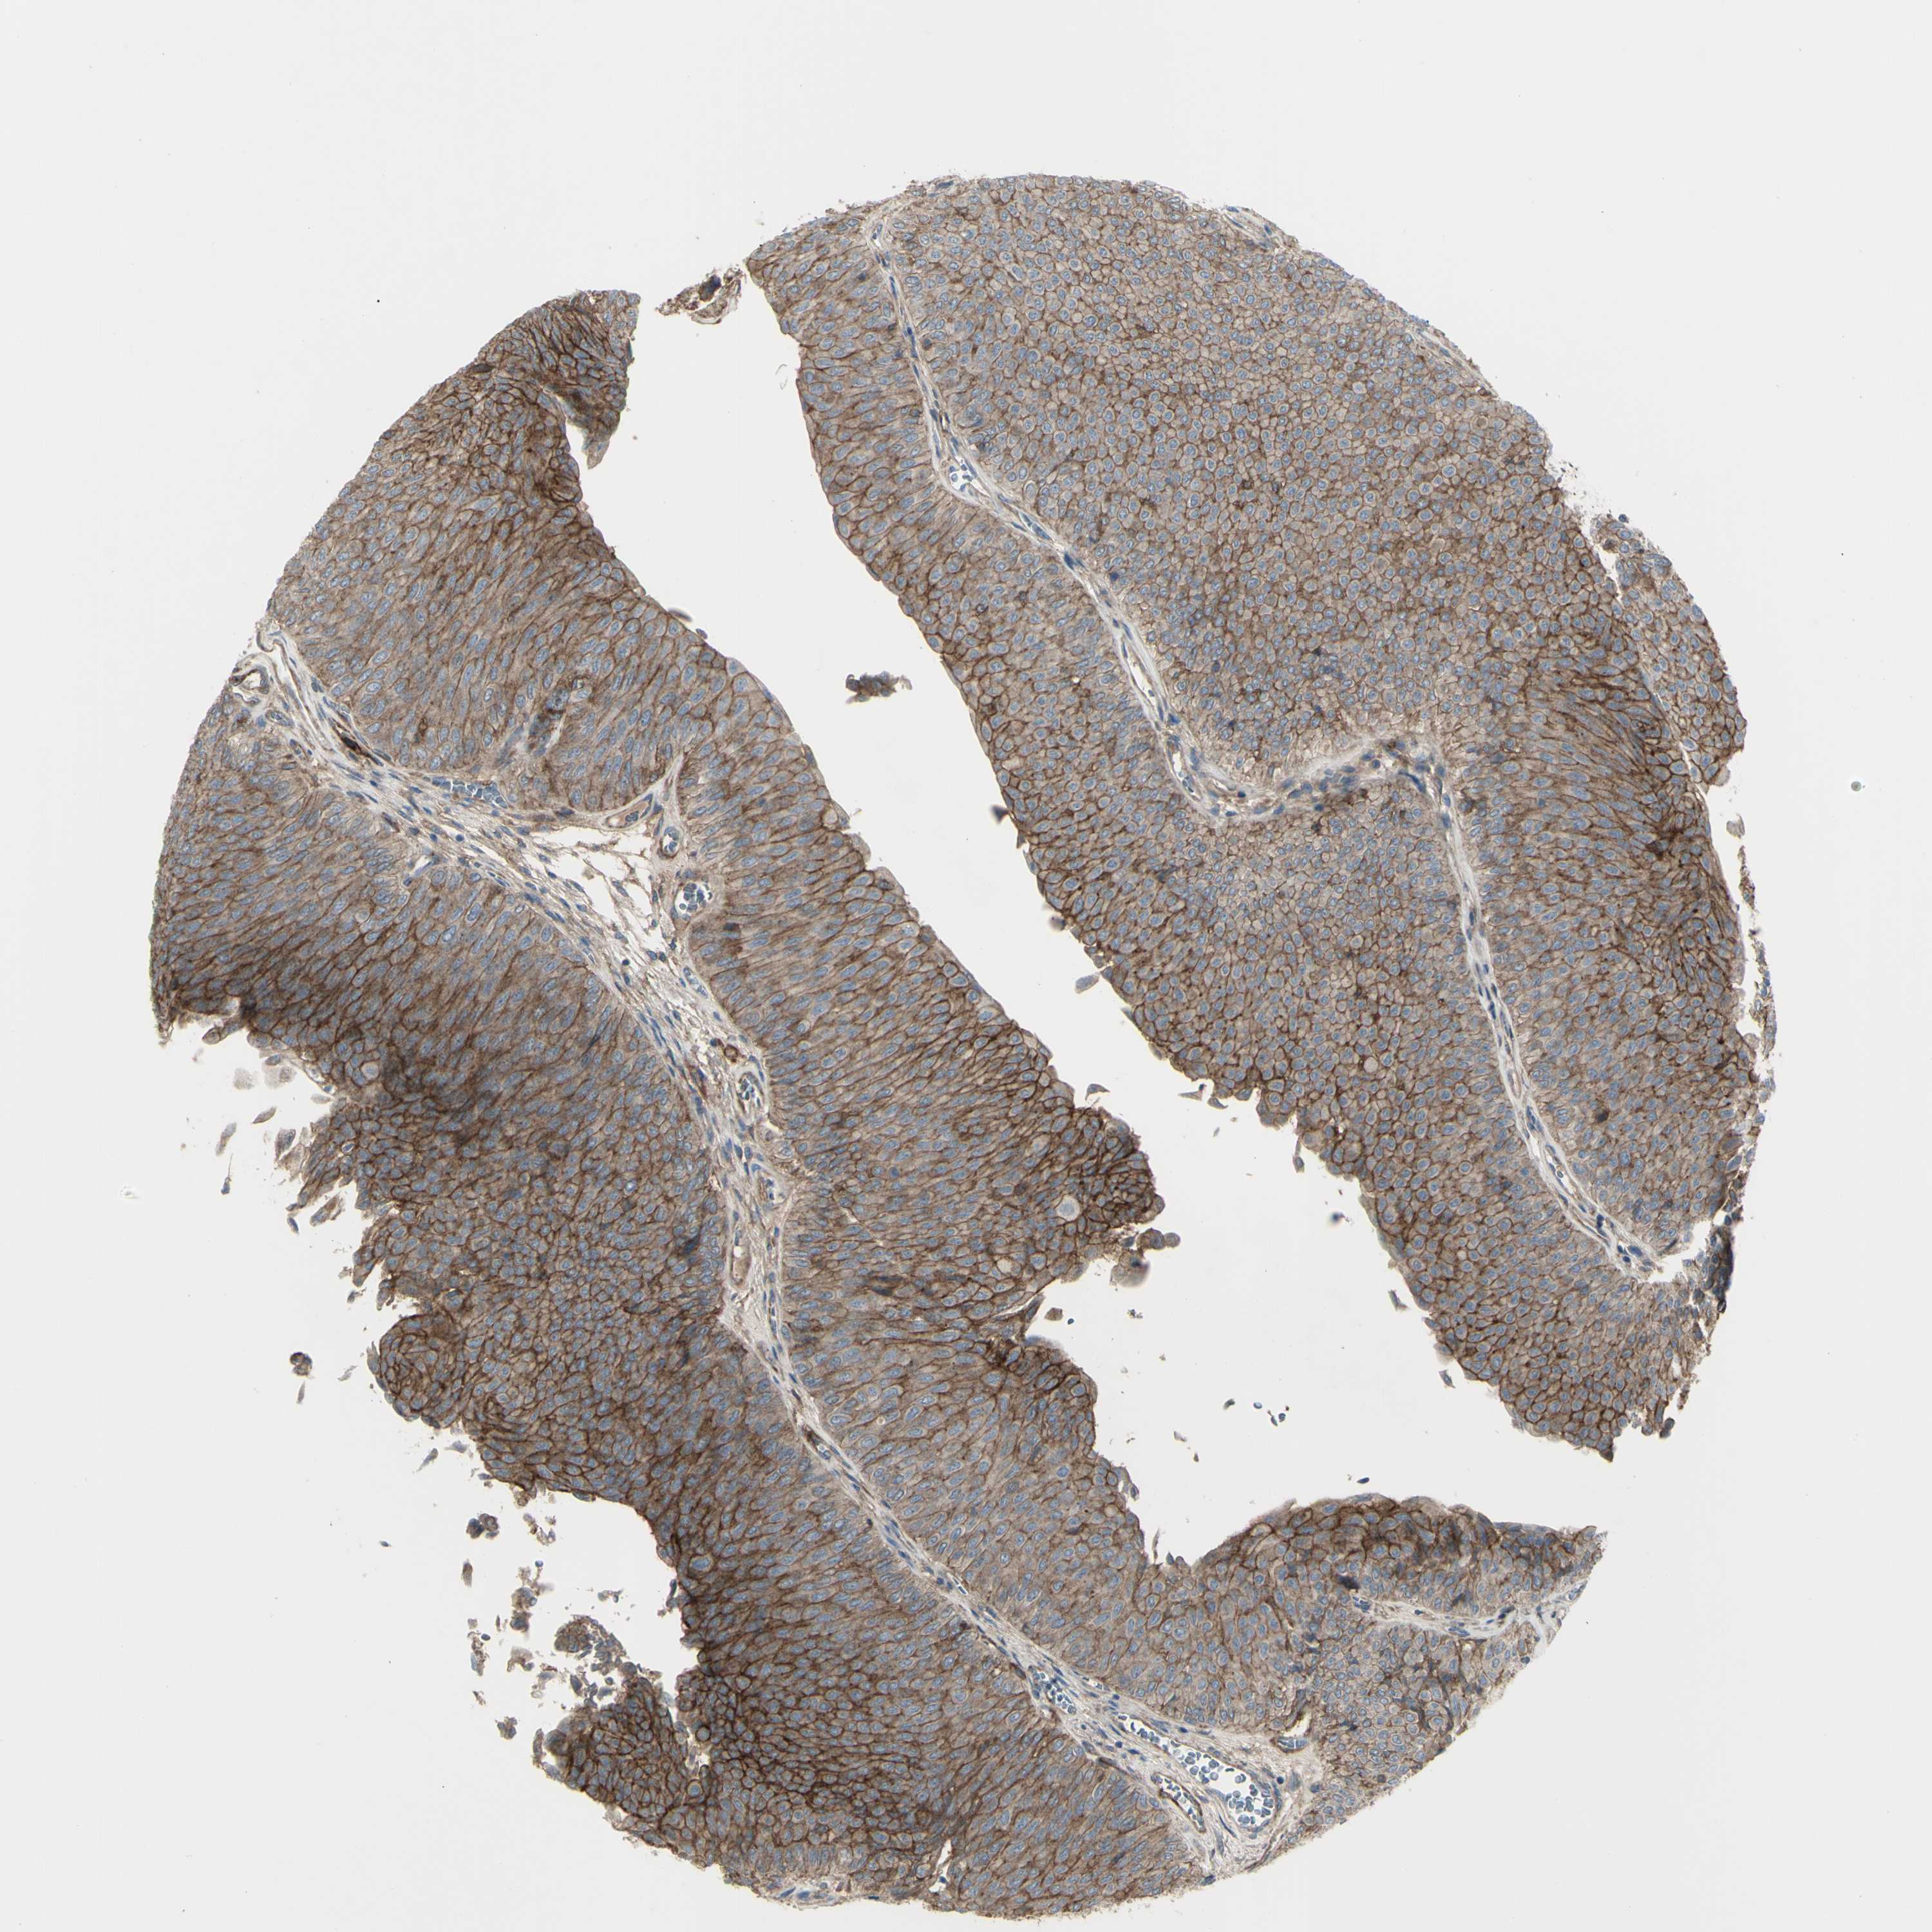

UROTHELIAL CANCER - Protein expressioni

A mouse-over function shows sample information and annotation data. Click on an image to view it in a full screen mode. Samples can be filtered based on level of antibody staining by selecting one or several of the following categories: high, medium, low and not detected. The assay and annotation is described here.

Note that samples used for immunohistochemistry by the Human Protein Atlas do not correspond to samples in the TCGA dataset.

Antibody stainingi

Antibody staining in the annotated cell types in the current human tissue is reported as not detected, low, medium, or high, based on conventional immunohistochemistry profiling in selected tissues. This score is based on the combination of the staining intensity and fraction of stained cells.

Each image is clickable and will lead to virtual microscopy that enables deeper exploration of all samples and also displays staining intensity scores, fraction scores and subcellular localization as well as patient and tissue information for each sample.

Antibody HPA009285

Antibody HPA017139

Antibody CAB017826

Staining

High

Medium

Low

Not detected

Intensity

Strong

Moderate

Weak

Negative

Quantity

>75%

75%-25%

<25%

None

Location

Nuclear

Cytoplasmic/membranous

Cytoplasmic/membranous,nuclear

Urothelial carcinoma, Low grade

Urothelial carcinoma, High grade